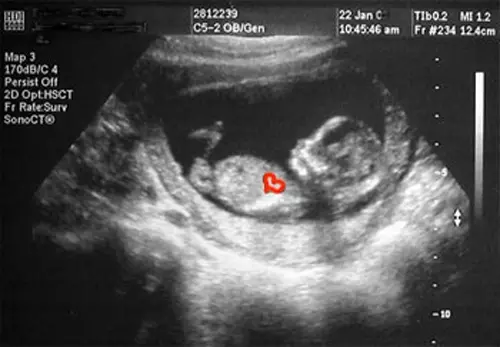

The program is divided into four levels: grade school, starting with kindergarten; fourth to sixth grades; seventh and eighth grades; and high school. Each presentation provides “fetal facts” that are geared for that particular age level and a live ultrasound with a pregnant woman and an ultrasound technician. Various speakers, including people who have adopted children and women who have had abortions, can be involved as well, depending upon the grade level.

“We got in through a science class,” she said. “We focused on fetal development – there was no Scripture or talk about abortion. I think that’s why it worked. We still used pregnant volunteers and did live ultrasounds. You don’t need to use Scripture to show the truth.”